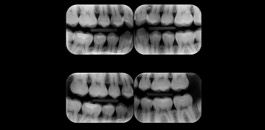

Indicada para avaliação detalhada das estruturas interproximais.